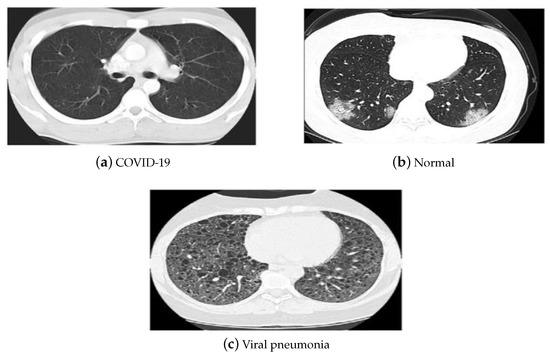

4. Utilized Data Sets